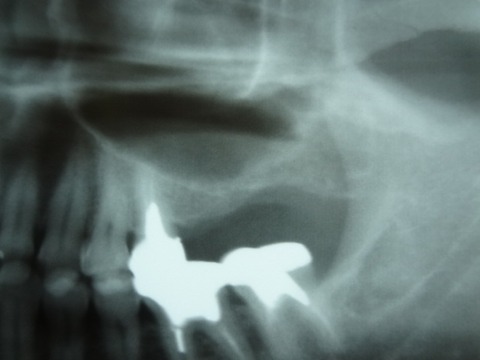

以下の写真は 先日 行ったソケットリフト症例です。

サイナスリフト症例となるべく 骨の薄い部分も存在する症例であります。

黄色の線で書いた上顎洞底の粘膜( シュナイダー膜)を破らないようにしてリフトアップさせます。

上顎骨とシュナイダー膜の間に インプラント体(フィクスチャー)と 骨補填材(将来 骨に置換され

るものです)を入れていきます。

バルーンリフトテクニックは使用しておりませんが、リフティングドリルと骨補填材の使用により、

全く患者様に負担の無い治療ができました。 治療時、治療後 共に殆ど痛みはなかった

ということでありました。